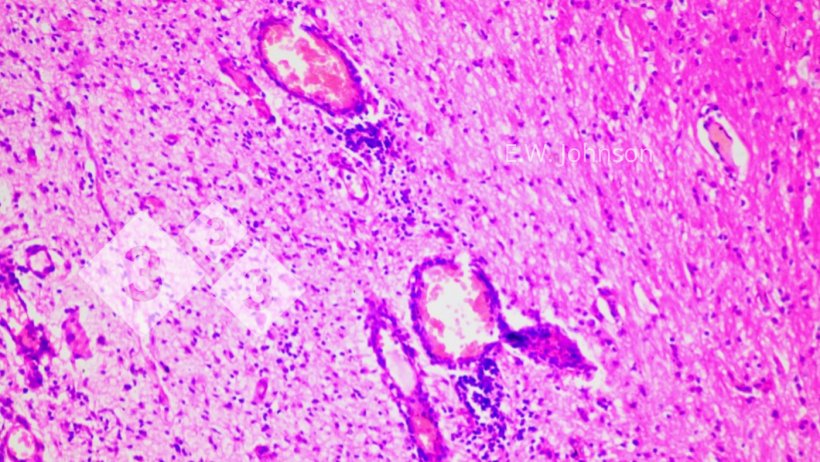

Image 2. Manchons périvasculaires et gliose. Cerveau.

L'examen microscopique du cerveau révèle une méningoencéphalite avec des manchons périvasculaires et une gliose (image 2) et une infiltration des méninges par des cellules inflammatoires mixtes mononucléaires et polymorphonucléaires (image 3). Image 3. Méningite avec des cellules mononucléaires et quelques cellules polymorphonucléaires. Cerveau.